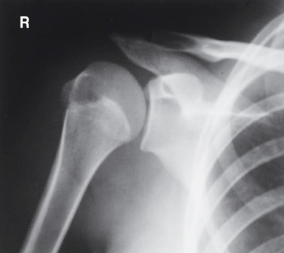

is this a normal or dislocated shoulder? how do you know?

normal, head of humerus superimposed over base of Y